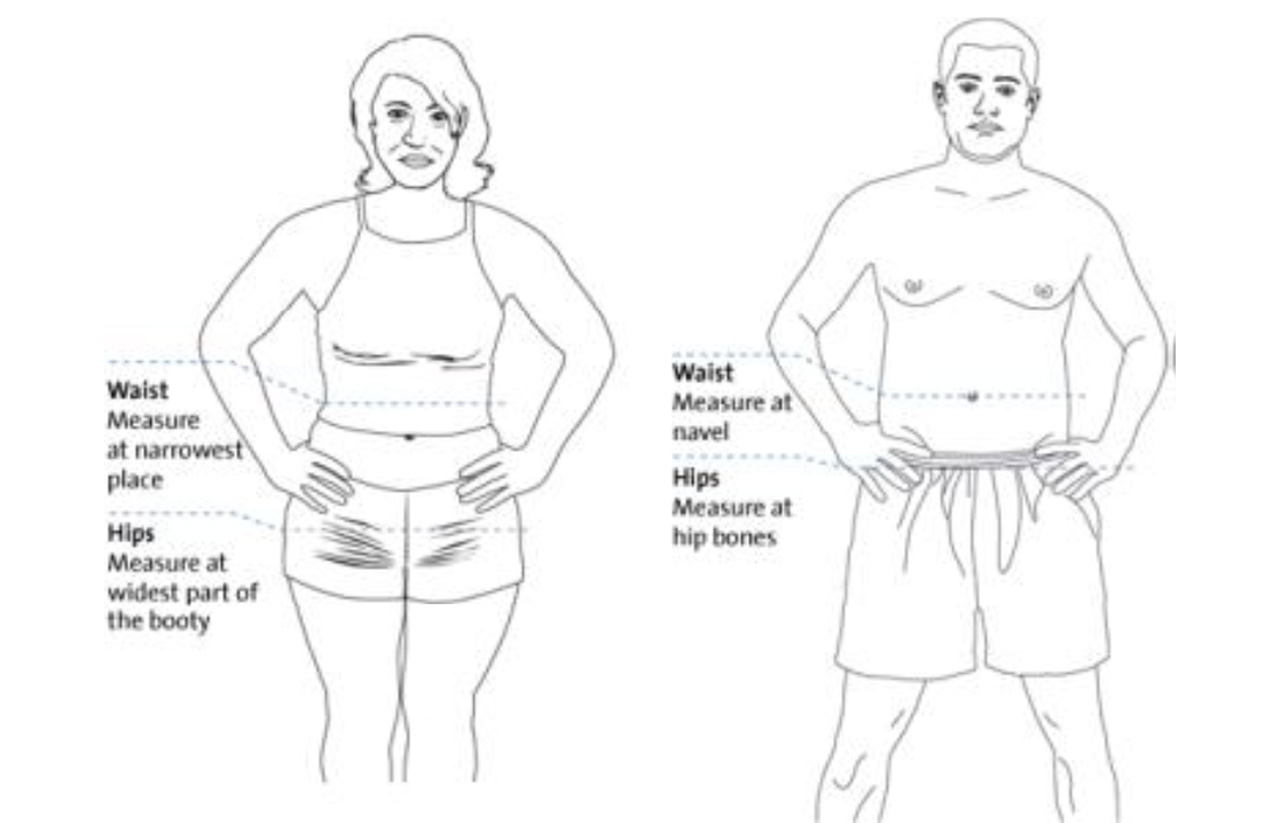

Taillen-Hüft-Verhältnis (WHR, waist to hipp ratio) und Bauchumfang (BU)

Diese beiden Parameter beschreiben das abdominelle Fettverteilungsmuster, welches eng mit kardiovaskulären Erkrankungen korreliert, da das viszerale Fett – das Fett der Bauchorgane, metabolisch aktiv ist.